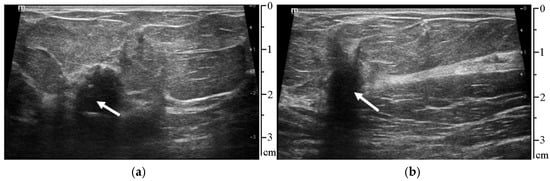

| Video Sequence | Correctly Detected Frames | Incorrectly Detected or Not Detected (Frames) |

|---|---|---|

| First video | 53 out of 60 (88.34%) | 7 out of 60 (11.66%) |

| Second video | 54 out of 60 (90.00%) | 6 out of 60 (10.00%) |

| Total all 52 videos | 2867 out of 3120 (91.89%) | 253 out of 3120 (8.11%) |